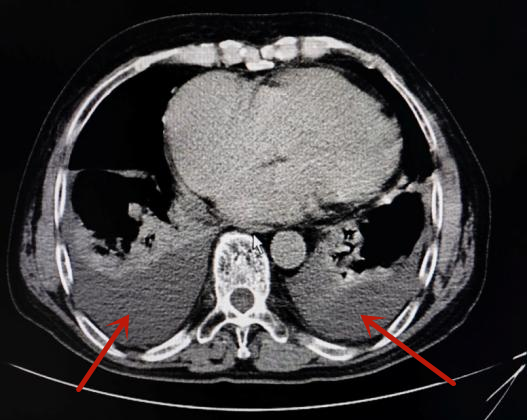

(双侧胸腔积液、心脏扩大)

询问病史得知,最近一个月来,李嗲嗲体力明显不如从前,步行100米都会喘气。医生立即为其完善胸腹部CT、心脏彩超及心电图等检查,结果显示李嗲嗲双侧胸腔有积液,心脏扩大,并伴有左心室舒张功能减退、心房颤动等,被诊断为心衰、房颤。